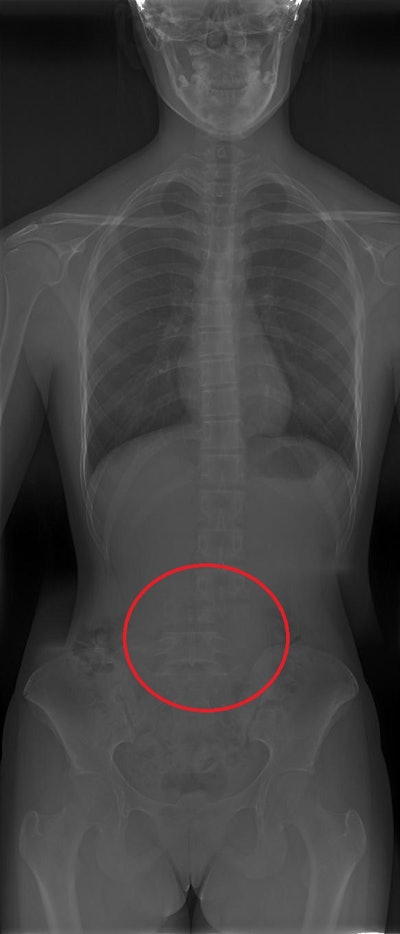

An x-ray device is now available that has a detector large enough to perform full-spine images with just one exposure to the patient. The researchers sought to evaluate the performance of the one-exposure system, compared with that of a traditional machine.

Two systems are used to perform full spine studies at the Madrid hospital: a General Electric Definium 8000 machine and a Fuji FDR Smart Suspension system, which allows full-spine scans to be performed in one shot. For the latter, the detector consists of three regular detectors placed together, so there is no need to move the x-ray tube and detector down the spine, thus reducing artifacts and presumably patient effective doses due to non-overlapping.